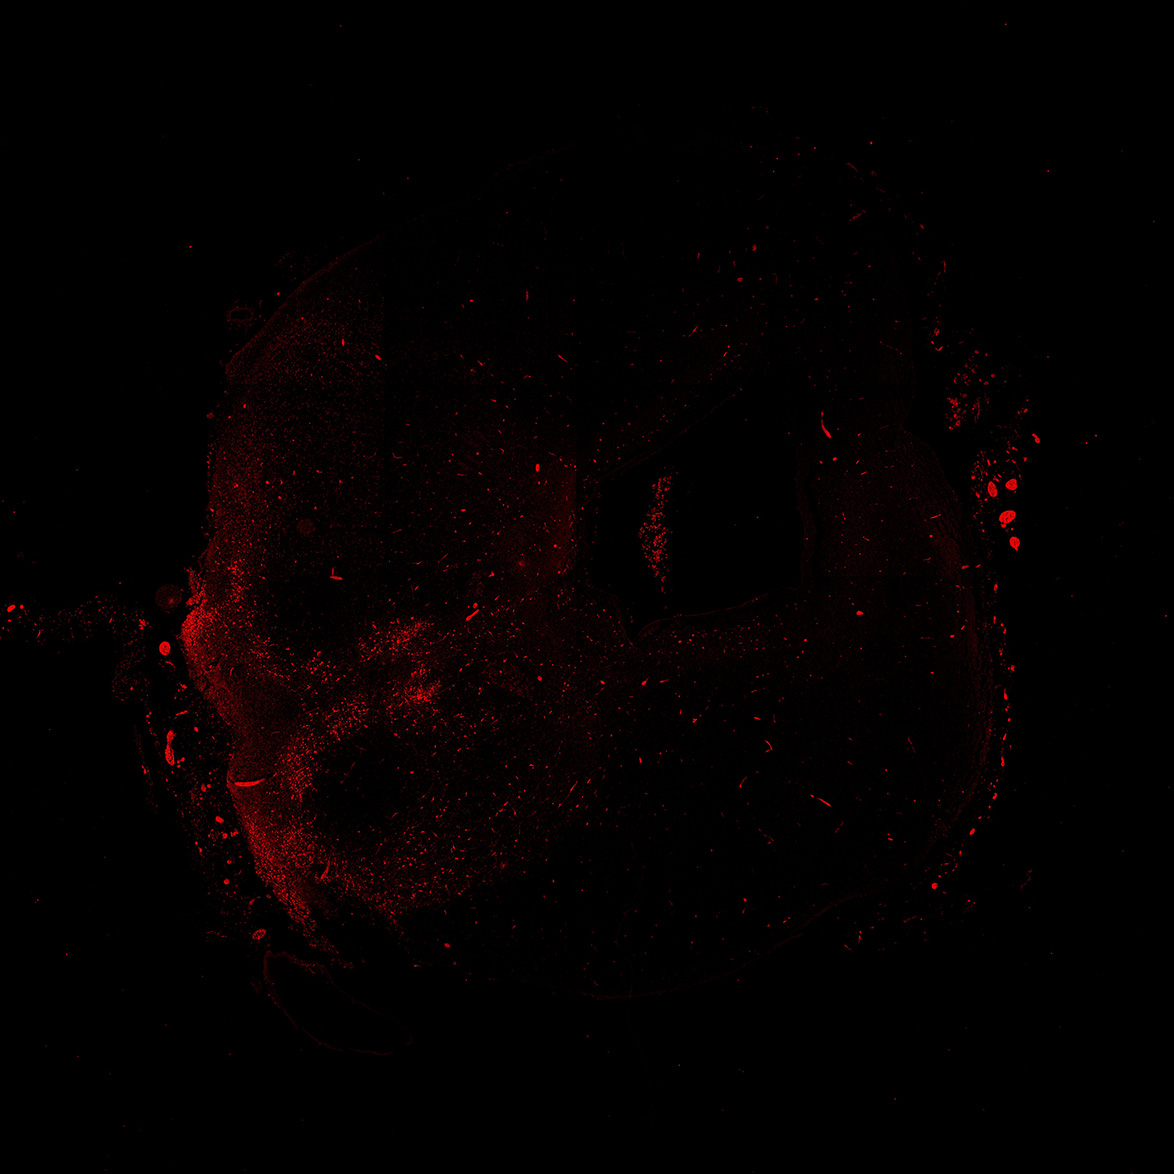

An anatomical analysis of the developing human midbrain from 6 post-conceptional weeks (PCW) to 22 PCW reveals increased tissue complexity, characterized by the emergence of dopaminergic nuclei, as highlighted by immunofluorescence analysis for tyrosine hydroxylase (TH).

TH

13PCW human midbrain